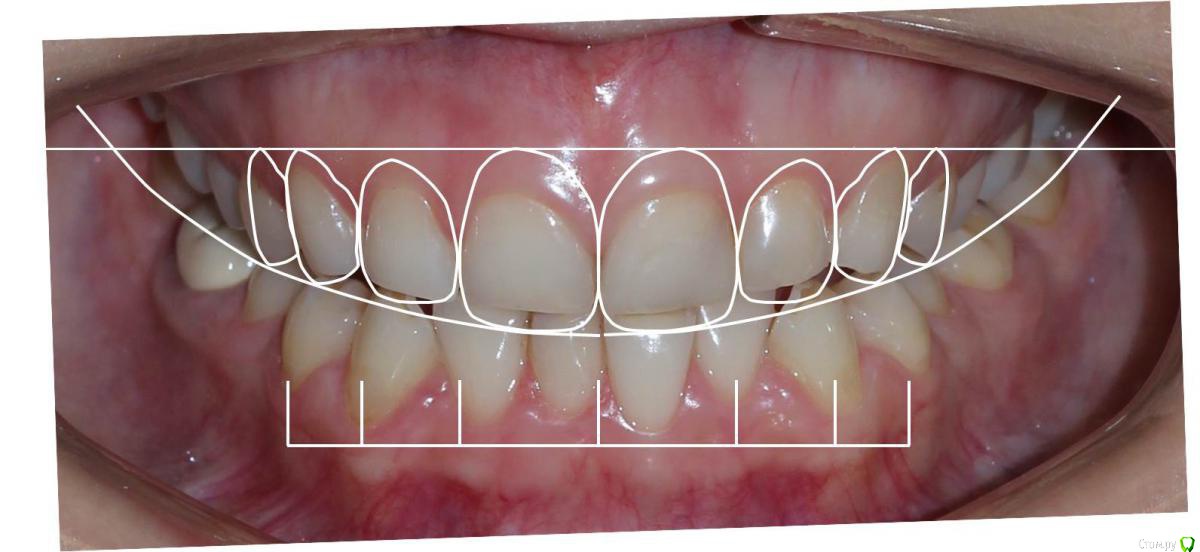

Сева северный Опубликовано 9 декабря, 2015 Поделиться Опубликовано 9 декабря, 2015 Ко мне обратилась молодая девушка, не довольная своей улыбкой. Был проведен этап планирования.... анализ улыбки ..(DSD), (wax up) и примерка (mock up)Проведенный этап...с мотивировал пациентку . 15 Ссылка на комментарий

Сева северный Опубликовано 11 декабря, 2015 Автор Поделиться Опубликовано 11 декабря, 2015 Почему не через зеркало?В принципе на вопрос уже ответили.... могу лишь добавить, что при (wax up) мы как правило воск добавляем, причем его слои, не всегда одинаковой толщины, поэтому темные зубы через (mock up) будет просвечиваться.Бывают варианты когда я наоборот не могу наносить воск+ мелкие косячки... в виде пор, фестончатых краев, небольшой ассимитрии. все это будет видеть пациент через зеркало. С расстояния.. 2-3 метра они с нивелируются. Я должен показать общую картину, именно улыбку. Сравните на прикрепленном примере... пришеечные косячки (mock up) которые я не стал исправлять, и как они не заметны на фото, с растояния 2 Ссылка на комментарий

Сева северный Опубликовано 11 декабря, 2015 Автор Поделиться Опубликовано 11 декабря, 2015 (изменено) Как вы определяете когда надо делать хир.удлинение коронки, а когда просто удлинить без хирургии. По стертым режущим краям,похоже что не было нарушения прорезывания...зондировали до ЦЭС? Или по десневой улыбке скромной решили пойти апикально?Я сделал только планирование.... Ход мысли был следующий: Длина центральных резцов 19-20 мм. Длина коронковой части зуба центрального резца 7-8 мм. Оптимальная длина 10.5. По результату пациентка с мотивирована на ортодонтию , с коррекцией gammy smile. Решение по хирургии, примем по результатам ортодонтии. Изменено 11 декабря, 2015 пользователем Сева северный 1 Ссылка на комментарий